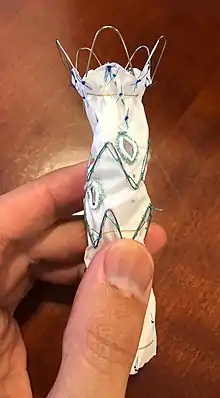

Endovascular aneurysm repair (EVAR) is a type of minimally-invasive endovascular surgery used to treat pathology of the aorta, most commonly an abdominal aortic aneurysm (AAA). When used to treat thoracic aortic disease, the procedure is then specifically termed TEVAR for "thoracic endovascular aortic/aneurysm repair." EVAR involves the placement of an expandable stent graft within the aorta to treat aortic disease without operating directly on the aorta. In 2003, EVAR surpassed open aortic surgery as the most common technique for repair of AAA,[1] and in 2010, EVAR accounted for 78% of all intact AAA repair in the United States.[2]

Dr. Juan C. Parodi introduced the minimally-invasive endovascular aneurysm repair (EVAR) to the world and performed the first successful endovascular repair of an abdominal aortic aneurysm on 7 September 1990 in Buenos Aires on a friend of Carlos Menem, the then President of Argentina. The first device was simple, according to Parodi: "It was a graft I designed with expandable ends, the extra-large Palmaz stent, a Teflon sheath with a valve, a wire, and the valvuloplasty balloon, which I took from the cardiologists." Parodi's first patient lived for nine years after the procedure and died from pancreatic cancer.[55][56] The first EVAR performed in the United States was in 1992 by Drs. Frank Veith, Michael Marin, Juan Parodi and Claudio Schonholz at Montefiore Medical Center affiliated with Albert Einstein College of Medicine.

The modern endovascular device used to repair abdominal aortic aneurysms, which is bifurcated and modular, was pioneered and first employed by Dr. Timothy Chuter while a fellow at the University of Rochester.[57] The first clinical series of his device was published from Nottingham in 1994.[58] The first endovascular repair of a ruptured abdominal aortic aneurysm was also reported from Nottingham in 1994.[59]